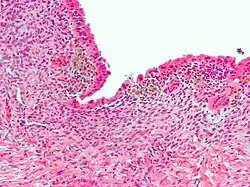

| Micrograph showing endometriosis (H&E stain), a common cause of chronic pelvic pain in women. | |